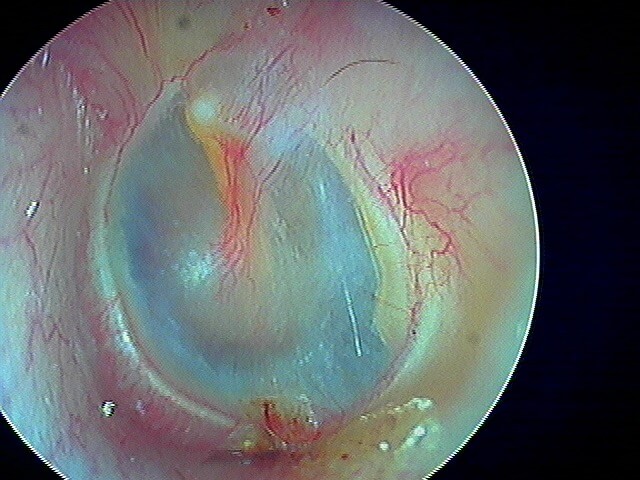

Ici une otite séromuqueuse gauche perforée cicatrisée à 1 mois (cicatrice inférieure)

Une otite séromuqueuse droite perforée (et non otite moyenne aiguë)

L' aspect est difficile à voir chez les enfants (j'utilise un endoscope 0° 2,7mm de diamètre d'où la petite image): c'est finalement une otite séromuqueuse gauche perforée et non otite moyenne aiguë.